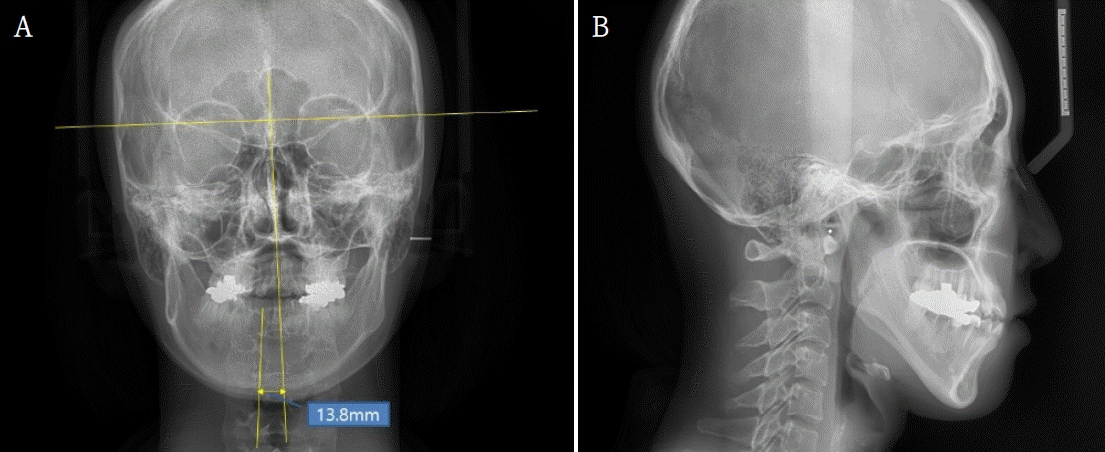

28세 여성이 안면비대칭과 턱관절의 불편감으로 내원하였다. 안모는 우측으로 비대칭이 관찰되었으며, 우측 턱관절부위의 관절잡음이 있었으며 26mm 개구 시 과두걸림이 있었다. 최대개구량은 48mm이고 우측으로 변위된 개구 양상을 보였다. 안면 CT와 X-ray 촬영 결과, 좌측 하악지가 우측 하악지에 비해 12.89mm 길었으며 관절까지의 방향이 우측 하악지에 비해 외측으로 향해 있는 것을 알 수 있었다(Fig. 1). 우측 하악체의 길이가 좌측에 비해 길고 이로 인해 하악 턱끝은 정중선에 비해 우측으로 13.8mm 편위되어 있었다. 그리고 교합평면은 좌측으로 기울어지고 구치부 반대교합과 전치부 절단교합이 존재하였다(Fig. 2). 안면비대칭과 턱관절원판의 정복성 전방변위로 진단하고 하악골의 비대칭과 교합평면의 개선을 위해 턱교정수술과 치아교정술을 계획하였다. 턱교정수술은 상악골 후상방(좌측: 3.5mm, 우측: 4.5mm)이동하고, 하악골은 후방(좌측: 17.5mm, 우측: 5.5mm) 이동하였다(Fig. 3). 턱끝성형술과 하악골 윤곽성형술을 통해 하악골과 안모의 대칭에 도움을 주었다. 하악골수술은 시 시상분할절골술을 이용하였으며, 관절과두가 포함된 근심골편을 재위치시켜주어 과두걸림을 해소하려 하였다. 수술 2주후 치아교정술을 시작하면서 개구연습을 진행하였으며 비대칭적 개구 습관의 교정을 위해 탄성고무줄을 이용하여 중심선에 맞게 진행하였다. 수술 6개월 후 평가 시, 안모의 비대칭은 개선된 결과를 보였으며(Fig. 4) 턱관절 부위의 과두걸림은 관찰되지 않고 정상범위 내의 개구 양상을 보였다.- 증례 2

32세 여성이 우측 턱관절의 통증과 개구제한을 주소로 내원하였다. 내원 전에 3차례에 걸쳐 각각 다른 의료기관에서 턱교정수술을 받은 경험이 있고, 음식물 저작이 힘들고 입이 비뚤어져 사회관계에도 문제가 있었다. 안모는 좌측으로 변위된 비대칭이 관찰되었고 교합은 상악골의 우측 변위, 하악골의 경사진 좌측 변위로 인해 치아 중심선 비대칭을 포함하여 전치부의 개방교합과 구치부의 반대교합이 관찰되었다(Fig. 5). 우측 관절부위 통증과 다수의 수술로 인한 저작근 주위 조직의 경직으로 인해 자발적 최대개구량은 23mm이었다. 파노라마방사선영상에서 우측 하악과두가 좌측에 비해 glenoid fossa으로 부터 떨어져 있고 전방으로 기울어져 있는 것을 관찰할 수 있었다(Fig. 6). 이전 하악골편 고정시 하악과두가 포함된 근심골편이 후방으로 위치하여 고정된 것과 상악골의 우측 변위되어 고정된 것을 개선시키기 위해 4번째 턱교정재수술(4th reoperation)과 치아교정술을 계획하였다. 상악골의 수술 시 하악골의 안정을 위해 후상방이동 2.5mm와 기울어진 교합평면의 개선을 위해 교합평면 수정1.5mm를 하였으며 동시에 상악의 비대칭 개선을 위해 좌측으로 1.5mm 측방이동하였다. 하악골은 기존의 골절선을 이용하여 골편을 분리한 후 변위된 우측 근심골편을 관절와에 재위치시키고 상악골의 위치에 따라 고정하였다. 수술 중 비대칭이 해소된 것과 개구량 45mm 확보된 것을 확인하였다. 수술 후 파노라마방사선영상과 3D CT영상에서 치아의 정중선이 일치하고 전치부 및 구치부의 반대교합이 해소된 것을 볼 수 있었다. 그리고 우측 하악과두가 관절강 내 재위치된 것과 하악지의 방향이 좌, 우측 비슷하다는 것을 확인할 수 있었다(Figs. 7 and 8). 수술 후 2주부터 개구연습과 치아 교정을 진행하였으며, 수술 후 3개월에 자발적 개구량 35mm 확인하였다. 다수의 수술로 인한 구강내 반흔 조직과 저작근 주위의 경결감으로 인해 적극적인 개구훈련을 하였으며 수술 후 6개월에 38mm의 개구량을 보였으나 통증은 없고 일상식이 가능하여 이후의 경과관찰에는 내원하지 않았다.- 증례 3

턱관절을 포함한 저작 부위의 비정상적 하중은 안면부 통증을 비롯하여 턱관절증, 관절염과 같은 턱관절 질환과 치아 파절, 보철물 및 치과 임플란트의 파절 등 여러 가지 문제를 야기할 수 있다. 이러한 턱관절 질환에 대해 몇 가지 가능한 원인이 제안되었지만 조절되지 않은 힘과 안면비대칭이나 부정교합과 같은 턱뼈의 구조적 문제는 관절의 생체 역학 변화에 기여하는 가장 흔한 병인학적 요인으로 생각할 수 있다[11]. 첫 번째 환자의 경우, 좌측 하악지가 우측에 비해 12.89mm 길었고 이 영향으로 하악골의 중심은 우측으로 편위되어 있었다. 이러한 경우, 대부분 짧은 쪽으로 하중이 많이 전달되어 턱관절 질환이 발생할 가능성이 높다. 이 환자는 상대적으로 짧은 하악지를 가진 우측에 관절 잡음을 동반하여 간헐적 과두 걸림이 있었다. 턱관절에 가해지는 과한 하중은 턱관절 원판이 전방 변위되고 원판 후방조직에 힘이 가해져 통증과 관절 잡음을 포함한 턱관절증을 일으킨다[20]. 하지만 비대칭이 크게 존재하는 경우, 반드시 이환측에만 턱관절 장애가 존재하는 것은 아닌데, 이것은 통증이나 불편감을 해소하기 위해 반대측으로 비틀어 저작한다던지 편측 저작을 한 결과일 것이다. 이런 현상은 첫 번째 환자와 반대의 비대칭을 가진 환자의 경우에서 관찰할 수 있었는데, 좌측으로 편위된 비대칭이 있었으나 반대측에 턱관절증이 있었던 경우이다(Fig. 11). 하악골의 열성장과 제2급 부정교합의 경우 정상교합에 비해 상대적으로 짧은 하악지와 하악과두로 인해 턱관절의 디스크 전위나 골관절염이 생기는 취약한 환경에 있는 것과 유사하게 비대칭 하악골에서 구조적으로 하중을 해소하는데 불리한 구조이다[16-19]. 이런 골격적 문제를 해결하기 위해서는 턱교정수술과 치아 교정이 필요할 수 있다. 턱교정수술에서 고려해야할 점은 틀어진 교합평면의 수정, 하악지의 관절에서 내려오는 방향과 측방으로 벗어나려는 힘의 조절 등이다. 상악골의 재위치 시 수술 후 비대칭을 해소하기 위한 하악의 위치를 고려하여 rotation, canting correction, shifting 등 3차원적으로 수술계획을 하여야한다. 그리고 하악골의 시상분할절골술 후 고정 시, 하악과두를 포함한 근심 골편이 관절내에서 앞뒤, 좌우 등으로 치우치는 힘으로부터 자유롭게 해야 하는데(freeing) 이 때는 근심골편과 원심골편 사이에 저항이 없도록 고정시켜야 한다. 상악골과 하악골이 정중선에 재위치되어도 하악골체의 부피 차이와 턱끝 부위의 모양 차이로 인한 안면비대칭은 하악골의 골체변연성형술과 턱끝 수술을 통해 상당부분 해소해줄 수 있다. 하악골의 시상분할절골술 이후 근심골편을 고정할 때 관절부의 위치를 잘못 설정하면 두 번째 환자의 경우처럼 수술 이후에 개구제한이 있고 해당부위의 턱관절에 통증이 있을 수 있다. 해당 환자는 좌측 하악과두가 glenoid fossa에서 전방으로 떨어져 위치되었는데 이것은 근심골편의 고정시 후방으로 밀려 고정된 결과 일 수 있다. 후방압력에 의해 원심 골편은 좌측으로 틀어지며 치아는 편측으로 비틀어져 전치부 개방교합과 구치부의 반대교합이 나타났으리라 추측된다. 이러한 이유로 관절의 원판은 전방변위되고 후방조직의 압력으로 통증을 느끼게 되는데, 교합력이 가해지면 과도한 힘이 아니더라도 구조적으로 통증과 턱관절증을 일으킬 수 있을 것이다. 또한 잘못 고정된 하악지의 경우, 관절에 전해지는 힘의 방향이 좌우 다를 수 있다. 첫 번째 사례와 같이 하악지의 길이가 양쪽이 다른 경우, 관절에 전달되는 힘이 짧은 측을 축으로 하중의 차이가 있어 이환된 쪽에 턱관절 질환이 발생할 수 있는 것을 살펴보았다. 이와 비슷하게 관절로부터 하악각으로의 방향이 서로 다른 경우, 하중 전달량의 차이로 턱관절질환이 생길 수 있다. 따라서 두 번째 사례에서처럼 하악지의 고정 시 양측의 각도를 비슷하게 설정해주는 것이 이후 턱관절에 양호한 하중 전달 구조에 유리하다(Fig. 7). 수술 이후 개구연습을 통하여 정상 범위의 개구량을 회복함에 있어 두 번째 사례에서는 고려해야할 점들이 있었다. 이전의 3번에 걸친 턱교정수술로 인해 잔존하는 근심골편의 양이 적었고 이로 인해 개구연습 시 과도한 힘에 의한 뒤틀림을 조심해야 했다. 그리고 골막과 저작근 주위의 반흔조직성 경결감으로 온열을 동반한 물리치료를 통해 저작근의 활성화 범위를 점차 넓혀갔다. 수술 전 상악골의 우측 편위로 인해 더욱 좌측으로 틀어져 보이던 하악을 보상성 개구활동으로 중심선을 맞추려고 했던 습관을 교정하기 위한 행동요법도 시행하였다. 행동요법은 습관의 교정으로 질병을 치료하는 방법이며 이중 바이오피드백은 자발적으로 제어할 수 없는 생리 활동을 공학적으로 측정하여 지각 가능한 정보로 생체에 전달하고, 그것을 바탕으로 학습, 훈련을 되풀이하여 자기 제어를 달성하는 기법이라 알려져 있다[21]. 턱관절 질환의 분야에서 바이오피드백은 수면 이갈이를 조절하는데 좋은 역할을 한다고 보고되어진다[22,23]. 세 번째 환자의 경우, 턱관절 부위의 통증과 심한 이갈이로 인해 치과의원에서 스플린트 치료, 보톡스 치료, 물리치료 등 수년간의 치료를 받았지만 나아지지 않아 바이오피드백을 통한 수면 이갈이를 관리하고자 하였다. 통증은 주로 측두부에서 있었으며, 수면 중 발생된 저작근의 과긴장으로 아침에 기상 후 두통이 심하였다. 과긴장되는 근육의 활동을 줄이기 위해 보톡스 주사가 주로 사용되는데 교근에만 주사하는 경우, 측두근의 활동이 강해져서 오히려 측두부에 통증을 호소하기 한다. 이 환자의 경우에도 이전 주사 부위가 아래쪽에 국한되어 있었다는 점은 교근의 위축이 오히려 측두근의 근육통을 발생시키지 않았나하는 추측을 해볼 수 있다. 보톡스 주사는 3개월 간의 효과를 가지고 있어서 그 이후에 관리가 되지 않으면 다시 저작근의 과긴장에 의한 턱관절 질환을 재발시킬 수 있다. 스플린트는 제작 후 사용하다가 수면에 방해가 되고 불편하다는 이유로 적극적인 사용이 힘들었다고 하였으며, 실제로 스플린트 자체가 수면 이갈이를 방지하기 보다는 치아를 보호하고 턱관절 부위에 간격에 의한 안정을 주기에 비기능적 저작활동을 차단하는데는 한계가 있다. 사용된 바이오피드백 장치는 수면 중 측두근의 활동을 근전도를 이용하여 실시간으로 측정하고, 일정 역치 이상의 과긴장이 감지되면 생체에 진동 자극을 주어 clenching이나 grinding을 억제하도록 설계되어 있다. 본 연구에서는 이러한 기능을 갖춘 상용화된 장치인 Goodeeps(Miraclare, Republic of Korea) [24]를 사용하였다. 사용 시작 후 3일까지 장치를 통해 이갈이가 있을 때 근전도에서 확인이 되었으나 부착 부위의 이물감과 진동의 세기 조정 단계의 불편감 등으로 수면 중 잠을 깨는 경우가 있었다. 이 기간 동안 유의미한 이갈이(4초 이상)는 4에서 13회 정도 있었고, 다음날 아침에 일어났을 때 불편감이 점점 감소하는 기분이 들었다고 한다. 5일차 부터는 장치를 사용하는데 크게 불편한 점이 없었고 사용 후 3주차에서부터 진동이 필요할 정도의 이갈이는 발생하지 않았다. 진동을 주어도 이갈이가 계속되면 주어지는 진동의 크기를 높여 이갈이가 멈출 때까지 진행되기도 하였다(Fig. 12). 비기능적 행동을 할 때 생체내로 신호를 주어 제어하는 방식의 바이오피드백은 수면 이갈이의 발생시 진동을 주어 근 활동을 멈추게 하고 이것이 반복되면 무의식 중에 학습이 되어 이후 비기능적 습관을 회피하지 않을까라고 추측해 볼 수 있다. 실제로 환자는 6주 이후 바이오피드백 장치를 사용하지 않은 상태에서도 저작근에 힘을 주는 것에 대한 인지와 경계를 하여 이전의 턱관절 질환이 줄었다고 하였으나, 이에 대한 근거자료가 부족하여 이후 연구가 필요하다고 생각된다.턱관절 질환이 있는 환자를 문진할 때 다수의 경우에서 본인의 과도한 저작력을 인지하지 못한다. 그들은 수면 중 이를 가는 것이 없다고 하고 평소에 지그시 깨물고 있는 습관이 있는지 알지 못한다. 또한 턱관절 질환이 있는 상태에서는 딱딱하거나 질긴 음식을 제대로 씹지 못하여 턱에 힘을 주지 않는데도 계속 아프다고 하는 경우도 있다. 이것은 환자가 수면 중에 clenching과 grinding을 하거나 이것의 연장으로 낮에도 무의식적으로 깨물고 있을 가능성이 높다. 이러한 경우, 바이오피드백 장치는 환자와 의사에게 근전도 데이터를 이용한 정확한 저작근의 활동을 제공하여 턱관절 치료의 진단에 도움을 줄 수 있고, 의료기관에서뿐만 아니라 실생활 환경에서 비기능적인 저작력을 측정할 수 있고 유해한 행동에 대해서 조절할 수 있기에 턱관절 질환의 행동치료에 있어서 큰 역할을 할 수 있다고 본다. 턱관절 부위에 계속되는 부하는 저작근의 통증과 관절의 내장증, 그리고 골관절염 등을 유발하고 치료 이후에도 재발하게 하는 주요 요인으로 작용하기 때문에 힘의 비대칭성과 비정상적 강도 및 빈도를 조절하는 것이 턱관절 질환 치료의 시작이라고 볼 수 있다. 특히 행동요법 중 하나인 바이오피드백 장치는 습관성 질환인 턱관절 질환의 진단 및 관리에 도움을 줄 수 있다.